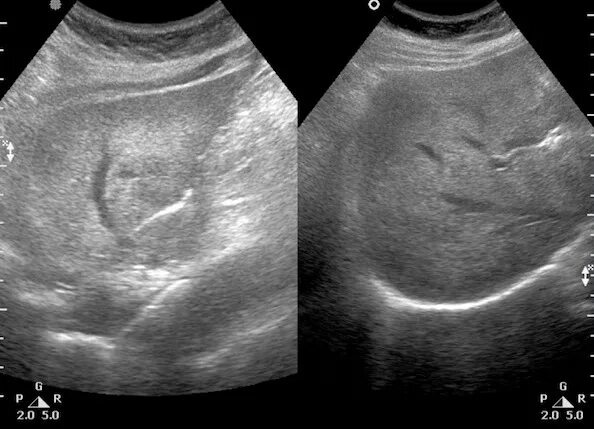

Эхо диффузные изменения